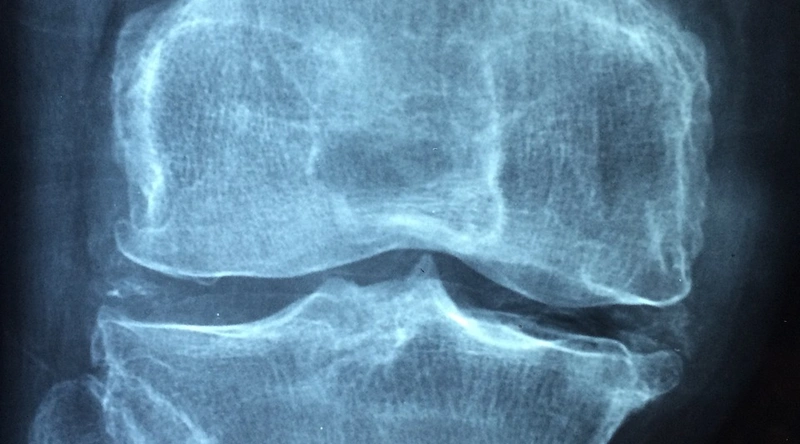

서론: 퇴행성 관절염에 대한 이해

퇴행성 관절염은 많은 사람들이 겪는 고질병으로, 주로 나이가 들면서 발생하는 관절의 퇴행성 변화로 인해 통증과 불편을 초래합니다. 이 질환은 관절의 연골이 점진적으로 손상되면서 염증과 통증을 동반하게 됩니다. 일상생활에서의 간단한 움직임조차 힘들어질 수 있으며, 이는 결국 삶의 질 저하로 이어질 수 있습니다. 따라서 퇴행성 관절염을 예방하고 관리하기 위한 방법을 찾는 것이 매우 중요합니다.

퇴행성 관절염은 단순한 노화 현상으로 간주되기 쉽지만, 이 질환은 다양한 원인에 의해 악화될 수 있습니다. 비만, 잘못된 자세, 지나치게 반복적인 동작 등은 관절에 많은 부담을 주어 퇴행 속도를 높일 수 있습니다. 그러므로 적절한 예방과 치료 방법을 통해 관절 건강을 지키는 것이 필수적입니다. 오늘은 퇴행성 관절염을 완치하기 위한 최고의 비법에 대해 여러 방면에서 알아보겠습니다.